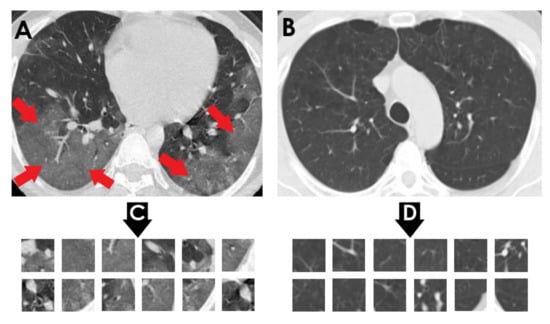

• COVID-CT dataset by [22] from GitHub (https://github.com/UCSD-AI4H/COVID-CT) (accessed on 2 December 2021): To assemble this dataset, COVID-19 (+) CT images were obtained from biRxiv and medRxiv repositories, posted from the 19 January 2020, to the 25 March 2020. The images were extracted using PyMuPDF software in order to maintain a high level of quality. The spatial sizes of the CT images range from 124 × 153 to 1485 × 1853. The meta data of each CT image (patient gender, age, medical history, scan time, location, severity of COVID-19, and radiology report) were manually collected. A total of 349 COVID-19 (+) CT images were obtained, from 216 patients. There are 169 patients whose age and 137 whose gender have been determined. The age distribution and the gender ratio of patients labeled with positive are shown in Figure 4 and Figure 5, respectively. It can be noted that the majority of COVID-19 patients are above the age of 30. In addition, the number of male patients is higher than the number of female patients, with 86 and 51, respectively. These patients are at varying stages of the disease on the 1st day through the 30th, with a majority as early as the 5th day and as late as the 10th day. The COVID-19 (−) CT images were collected from Radiopaedia website, from two other datasets (LUNA and MedPix), and from other articles and texts accessible through PubMed Central. A total of 463 COVID-19 (−) CT images were obtained from 55 patients. A comparison of COVID-19 (+) and COVID-19 (−) patients is shown in Figure 6. In Figure 6A, we can observe multiple patchy ground-glass opacities in bilateral subpleural areas. In Figure 6B, the chest CT scan shows the lungs with normal controls. In Figure 6C,D, we compare the patches from infected areas with those from non-infected areas, respectively. Our proposed system should subsequently be able to detect COVID-19 (+) patients by distinguishing between CT scans of patients infected with COVID-19 and those that are not.

Figure 6. (A) Shows a CT of the lungs of COVID-19 (+) patient, in which there are multiple patchy ground-glass opacities in bilateral subpleural areas indicated by red arrows. (B) Represents a CT of the lungs of a COVID-19 (−) patient with normal controls. (C) Depicts infected patch samples. (D) Reflects non-infected patch samples. COVID-CT dataset [22] is the source for these images.